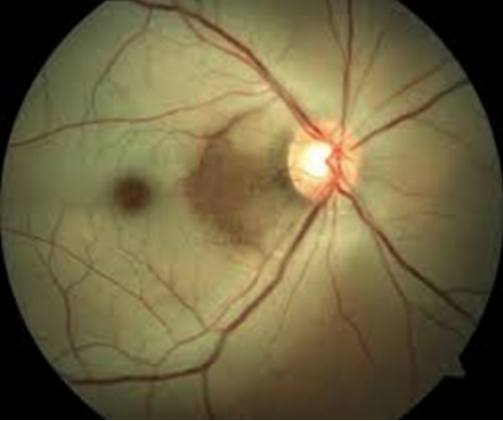

DMRI de fase cicatricial.